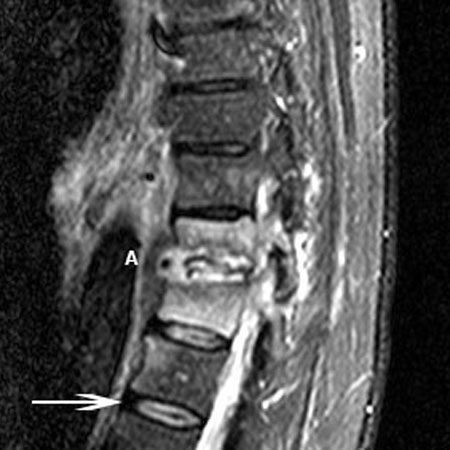

- RNM:

hérnia de disco

estenose da coluna vertebral, hipertrofia das facetas articulares e/ou ligamento amarelo com correspondente diminuição da dimensão do diâmetro do canal vertebral

- RNM com ou sem contraste:

compressão da cauda equina

- RNM da coluna vertebral:

compressão da medula espinhal